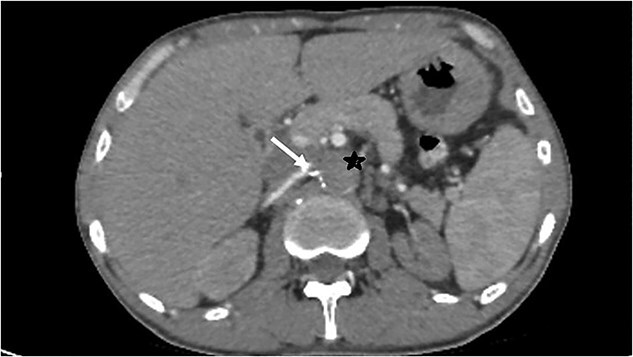

Lerich综合征,又称主动脉-髂闭塞综合征,是下肢闭塞性动脉病变中的一种特殊疾病,定义为主动脉-髂连接处血栓性闭塞。我们报告一例60岁的高血压病患者,慢性吸烟者。他入院接受肾功能衰竭评估,确诊为慢性肾病。此外,由于肾脏超声显示肾脏不对称(4,9 cm),要求行CT血管造影,确诊为肾动脉狭窄的Lerich综合征。进行了包括病因学在内的补充评估,未发现异常。治疗上,患者接受间歇性血液透析和治疗性抗凝治疗。我们的病例是莱里奇综合征罕见而偶然的发现。

Lerich syndrome, also known as aorto-iliac obliteration syndrome, is a specific entity among obliterative arteriopathies of the lower limbs, is defined as thrombotic occlusion of the aorto-iliac junction. We report a case of 60-yearold patient, chronic smoker with hypertension disease. He was admitted for an assessment of renal failure, in whom the diagnosis of chronic kidney disease was confirmed. Moreover, in the presence of renal asymmetry (4,9 cm) on renal ultrasound, a CT angiography was requested, confirming the diagnosis of Lerich syndrome with renal artery stenosis. A complementary assessment, including etiological one was performed, revealing no abnormalities. Therapeutically, the patient was placed on intermittent hemodialysis and curative anticoagulation. Our case represents a rare and fortuitous discovery of Lerich syndrome.